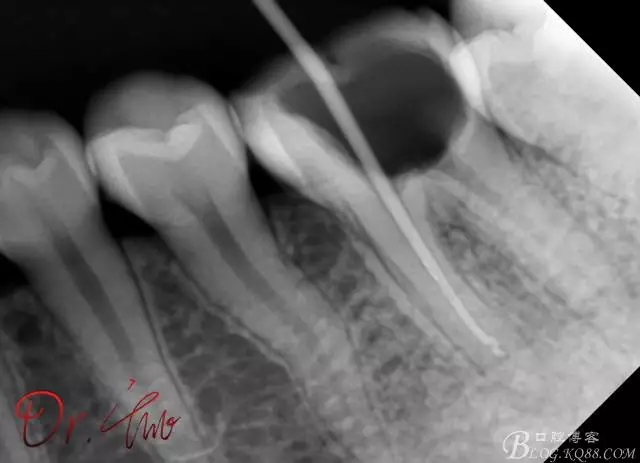

拍片確定長度

640.webp (1).jpg